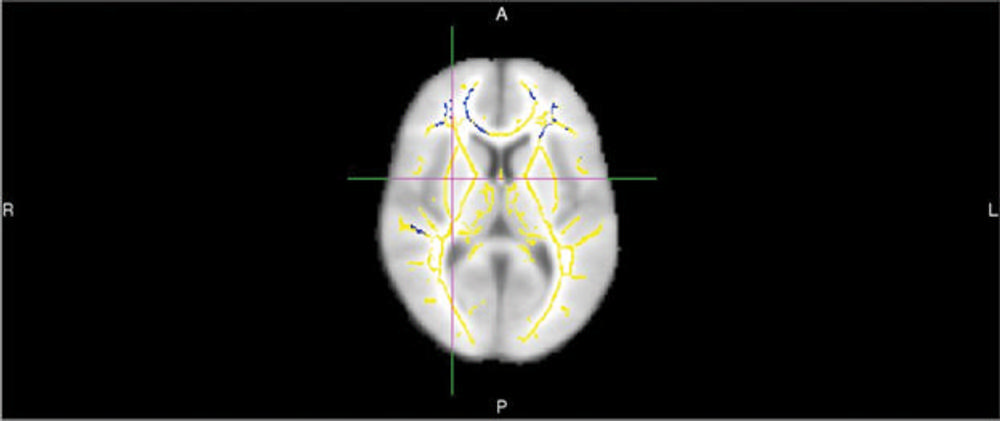

Common predictive models like standardized questionnaires used to measure cognition and tests for the APOE4 gene have limitations and—with accuracy rates of about 70-71 percent—fail to identify many people who go on to develop the disease.MRI exams of the brain using diffusion tensor imaging (DTI) are a promising option for analysis of dementia risk. DTI provides different metrics of white matter integrity, including fractional anisotropy (FA).

“With DTI you look at the movement of water molecules along white matter tracts, the telephone cables of brain,” Dr. Raji said. “When these tracts are not well connected, cognitive problems can result.”

For the new study, Dr. Raji and colleagues set out to quantify differences in DTI in people who decline from normal cognition or mild cognitive impairment to Alzheimer’s dementia compared to controls who do not develop dementia. They performed brain DTI exams on 61 people drawn from the Alzheimer’s Disease Neuroimaging Initiative, a major, multisite study focusing on the progression of the disease. About half of the patients went on to develop Alzheimer’s and DTI identified quantifiable differences in the brains of those patients. People who developed the disease had lower FA compared with those who didn’t, suggesting white matter damage. They also had statistically significant reductions in certain frontal white matter tracts.